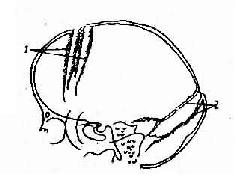

图2-23 儿童颅内高压所致颅缝分离

1.冠状缝 2. 人字缝